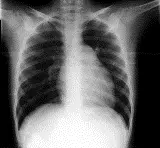

Ακτινογραφία θώρακα

Στην ακτινογραφία θώρακα είναι διευρυσμένες οι κεντρικές αρτηρίες με απότομη διακοπή του, σαν κλαδεμένο δέντρο.